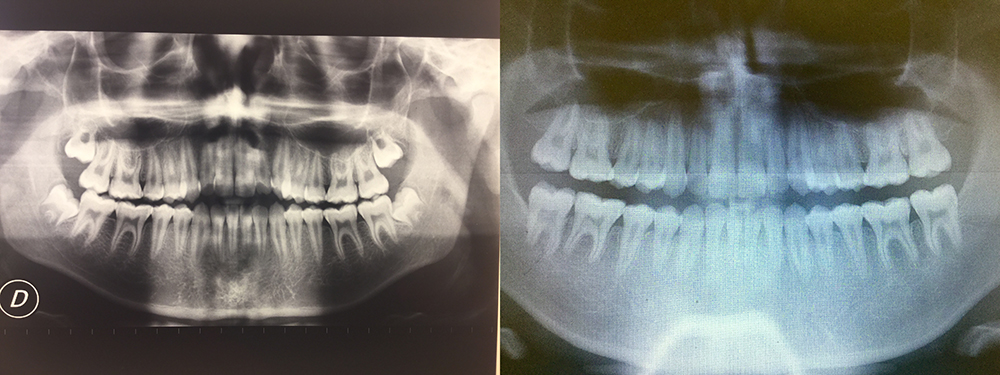

Notevole rilevanza hanno anche gli interventi di estrazioni spesso complicate particolarmente le avulsioni degli ottavi denti, oltre che la piccola chirurgia endodontica per rimuovere infezioni apicali altrimenti non aggredibili.

Rimozione denti del giudizio